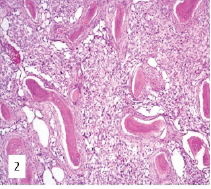

Histological Dedifferentiation in Recurrent Adamantinoma of the Tibia: A Case Report

Pavithra Ethirajan , Archana Lakshmanan

………………………………p.107-110